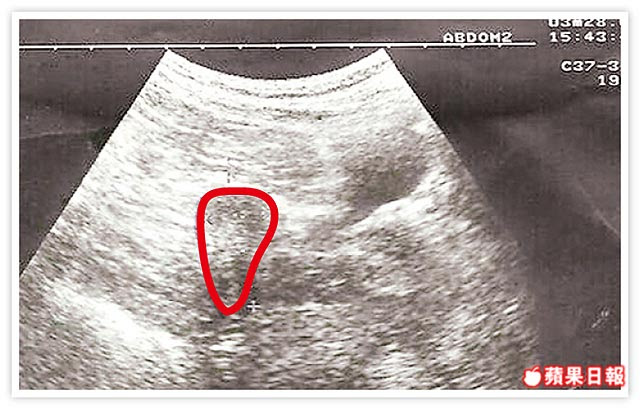

婦子宮萎縮如桃 奇蹟產女 兒時長瘤放療變小 借卵生子成功著床 博元婦產科不孕症試管嬰兒中心蔡鋒博醫師合法借卵生子,受精卵順利在她又小又硬的子宮內著床,但因子宮實在太小,懷孕二十六周就破水,安胎到二十八...